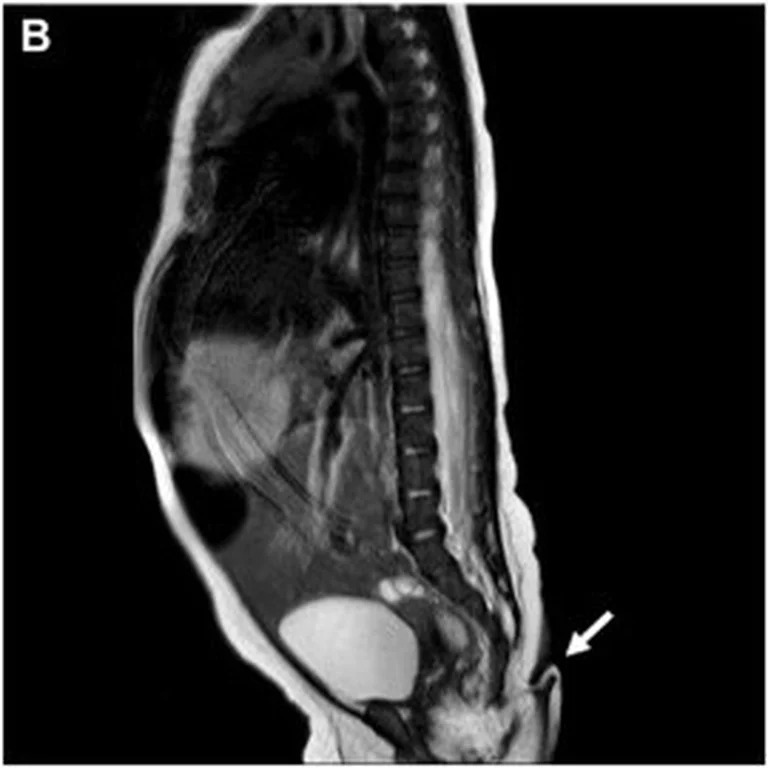

Asimismo, la resonancia magnética practicada no reveló anormalidades cerebrales, además, fue negativa para disrafismo posterior, y presentó médula espinal y cono medular de características normales. Entre tanto, la exploración auditiva y cardíaca fue normal, es decir: una bebé sana, por lo que fue dada de alta para seguimiento ambulatorio.